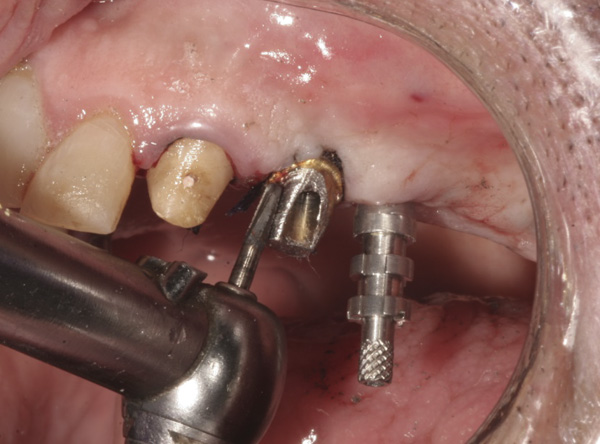

Background: This case had similar recession problems as the previously mentioned cases. Although the abutments were re-prepared intraorally to follow the new tissue margins, the decision was made to impress outside the mouth to avoid manipulation of the patient’s thin biotype tissue. Each custom abutment was removed and healing abutments were immediately inserted to avoid collapse of the tissues.

Results: Each custom abutment was placed on an implant fixture analog. Figure 6 shows the newly prepared abutment on its analog with a large-sized copper band to support impression material (alternatively, a stock quadrant impression tray could be used to provide support for the impression material). Figure 7 shows the custom abutment with cotton and wax placed to prevent impression material from entering the screw-access chamber, and Figure 8 illustrates the impression technique. This avoids the need to place retraction cord in the sulcus around the implant. This technique is also useful for adding to the margins of the provisional.

Figure 13 Temporary cylinders screwed to implants.

Figure 13

Figure 14 The cylinders luted to prefabricated acrylic shell.

Figure 14